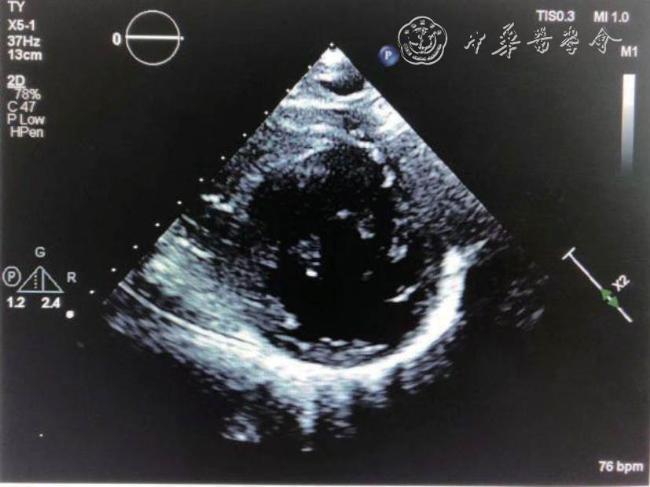

10例患者的超声心动图特点如下:(1)10例均表现为乳头肌水平以下的左心室组织消失,乳头肌直接附着于左心室“心尖部”呈复杂的网格状(图1,2)。(2)10例均表现为左心室形态异常,左心室“心尖部”圆钝而不尖,长径缩短,横径扩大,左心室呈球形,9例患者左右径和(或)前后径均增大:其中8例患者(病例1、2、3、4、5、7、8、10)左心室前后径及左右径均增大,1例患者(病例6)左心室左右径增大。另1例患者(病例9)各房室腔内径均偏小,但是相对长径缩短,横径增大。10例球形指数(spherical index,SI)即左心室长轴与短轴的比值(正常值>1.5)均减小(其中6例患者比值<1,1例患者比值≈1,其他3例患者比值分别为1.24、1.40、1.46,表2)。室间隔呈弧形向右心室膨出,室间隔及左心室壁厚度不均,10例患者室间隔及左心室壁最薄处厚度变薄,平均值为(4.2±1.2)mm;10例患者左心室侧壁及心尖部室壁均偏薄,侧壁厚度平均值(4.6±1.5)~(6.2±1.4)mm;左心室心尖部室壁厚度平均值(4.3±1.1)~(6.2±1.4)mm;其中8例患者室间隔均变薄,厚度平均值(5.1±1.4)~(6.5±1.5)mm,2例患者(病例5、9)室间隔厚度在正常范围(8~10)mm。(3)10例均表现为右心室形态异常,右心室狭长(患者右心室上下径均超过左心室上下径),向左后下方延伸,包绕短缩的左心室心尖部,整个心脏心尖部由右心室构成,由于室间隔向右膨凸,右心室中部内径偏小(图3)或者处于正常低值。

图1 超声心动图示乳头肌直接附着左心室心尖部

图3 心室形态异常的二维超声心动图图像。图a示左心室心尖部位圆钝而不尖,长径缩短,乳头肌直接附着于左心室心尖部;图b示左心室横径扩大,长径缩短,整体呈球形,右心室狭长,向左后下方延伸,包绕短缩的左心室心尖部,整个心脏心尖部由右心室构成。室间隔变薄,呈弧形向右心室膨出,右心室中部内径偏小